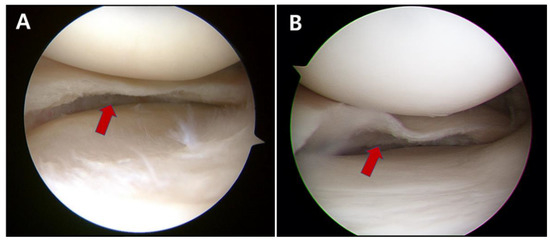

:1. Introduction

2. Materials and Methods

2.1. Study Participants